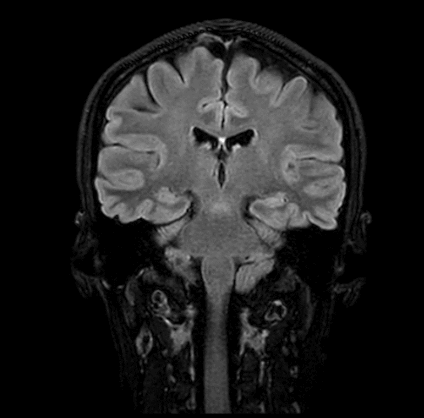

Wie sind die Graustufen auf dem MRT-Bild zu deuten?

Das Gewebe stellt sich in den unterschiedlichen Sequenzen je nach Signal in verschiedenen Grautönen dar.

Beispiele von MRT Aufnahmen des Kopfes

Die weißen Flecken, die man auf MRT-Bildern sieht, können viele Ursachen haben. Im Falle einer MRT vom Kopf können die weißen Punkte unter anderem als Liquor (Hirnwasser), Narbe oder Entzündung gedeutet werden.